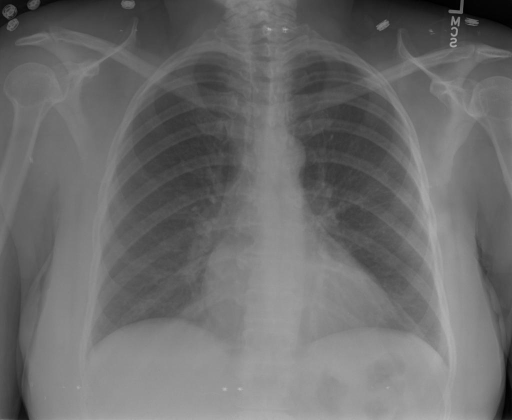

## 本文贡献  - 借助ChatGPT以及公开的数据集,我们构造了一个`X光影像-诊断报告`对的医学多模态数据集; - 我们将构建的中文胸部X光片诊断数据集在[VisualGLM-6B](https://github.com/THUDM/VisualGLM-6B)进行微调训练,并开放了部分训练权重用于学术研究; ## 数据集 - [MIMIC-CXR](https://physionet.org/content/mimic-cxr-jpg/2.0.0/)是一个公开可用的胸部X光片数据集,包括377,110张图像和227,827个相关报告。 - [OpenI](https://openi.nlm.nih.gov/faq#collection)是一个来自印第安纳大学医院的胸部X光片数据集,包括6,459张图像和3,955个报告。 在上述工作中,报告信息都为非结构化的,不利于科学研究。为了生成合理的医学报告,我们对两个数据集进行了预处理,并最终得到了可以用于训练的**英文报告**。除此之外,为了更好的支持中文社区发展,借助ChatGPT的能力,我们将英文报告进行了中文翻译,并最终形成了可用于训练的数据集。 |数据集|数量|下载链接| |:-|:-|:-| |MIMIC-CXR-zh|-|-| |OpenI-zh|6,423|[诊疗报告](./data/Xray/openi-zh.json) 、[X光影像](https://pan.baidu.com/s/13GBsDMKf6xBZBSHpoWH_EA?pwd=k9sh)| ## 快速上手 1. 安装环境 ```bash # 安装依赖 pip install -r requirements.txt # 国内换源安装依赖 pip install -i https://mirrors.aliyun.com/pypi/simple/ -r requirements.txt ``` 此时默认会安装`deepspeed`库(支持`sat`库训练),此库对于模型推理并非必要,同时部分`Windows`环境安装此库时会遇到问题。 如果想绕过`deepspeed`安装,我们可以将命令改为: ```bash # 安装依赖 pip install -i https://mirrors.aliyun.com/pypi/simple/ -r requirements_wo_ds.txt # 安装SwissArmyTransformer pip install -i https://mirrors.aliyun.com/pypi/simple/ --no-deps "SwissArmyTransformer>=0.3.6" ``` 2. 模型推理 CLI推理: ```python python cli_demo.py --from_pretrained checkpoints/finetune-XrayGLM-05-25-01-04 --prompt_zh '详细描述这张胸部X光片的诊断结果' ``` 更多[参数](https://github.com/WangRongsheng/XrayGLM/blob/main/cli_demo.py#L16) ## 效果展示 影像诊断: |X光影像|诊疗报告(医生)|XrayGLM| |:-|:-|:-| ||根据X射线图像,心脏大小正常,肺部看起来很清晰。已经排除了肺炎、积液、水肿、气胸、腺病、结节或肿块的存在。该发现表明一切正常。换句话说,总体印象是胸部正常。|X光片显示,心脏大小正常。肺部没有气胸或胸腔积液的证据。骨骼结构看起来没有任何异常。总的来说,X光片表明没有发现急性心肺疾病的迹象。| ||X光图片显示没有扭曲的区域、可疑的骨质不透明度或胸腺积液。心脏大小轻微增大,但非常稳定。此外,没有气胸的证据,肺野也正常。总体来说,X光片显示没有急性心脏异常,但要注意轻微的心脏扩大。|X光片显示,心脏大小正常。肺部和纵隔轮廓清晰,没有气胸或胸腔积液的证据。骨骼结构完整,没有任何急性异常。| ||心影形态在正常范围内。没有急性骨质异常。有可能出现没有明显的吸水或肺实质状况的线索。没有大面积积液或气胸。有可能怀疑其有误吸或肺实质问题。为了确诊和治疗,可能需要进行适当的影像学随访。|心脏大小正常,肺部和纵隔轮廓清晰。没有急性异常或活动受限的证据。没有任何明显的气胸、胸腔积液或肺不张的迹象。此外,也没有发现任何局灶性骨质异常或其他急性疾病。| 多轮对话: |X光影像|诊疗报告(医生)| |:-|:-| ||右侧主动脉突出观察到。心脏大小正常。胸部未发现明显的肺气肿、胸膜积液或可疑的肺部病变。报告指出已知右侧主动脉情况正常。| ```bash >> X光影像路径:./data/Xray/861_1.png >> 用户:这是一张什么图? >> XrayGLM:这张图片显示的是一张肺部检查的X光片。 >> 用户:请描述这张胸部X光片的诊断结果 >> XrayGLM:心脏大小正常,肺部清晰。没有急性心肺疾病的证据。 >> 用户:是否存在肺气肿? >> XrayGLM:没有肺气肿。心脏大小正常,肺部清晰。没有发现急性心肺疾病的证据。 >> 用户:平时饮食该注意什么? >> XrayGLM:饮食应该健康,均衡。建议增加蛋白质的摄入量,因为蛋白质有助于维持肌肉和骨骼的健康。多食用蔬菜、水果、全谷物以及健康的脂肪来源如橄榄油、鱼类等可以帮助获得足够的维生素和矿物质。此外,避免过度饮酒或吸烟,这些习惯可能会对心脏健康产生负面影响。 ``` ## 项目致谢 1. [VisualGLM-6B](https://github.com/THUDM/VisualGLM-6B)为我们提供了基础的代码参考和实现; 2. [MiniGPT-4](https://github.com/Vision-CAIR/MiniGPT-4)为我们这个项目提供了研发思路; 3. ChatGPT生成了高质量的中文版X光检查报告以支持XrayGLM训练; 4. [gpt_academic](https://github.com/binary-husky/gpt_academic)为文档翻译提供了多线程加速; 5. [MedCLIP](https://github.com/RyanWangZf/MedCLIP) 、[BLIP2](https://huggingface.co/docs/transformers/main/model_doc/blip-2) 、[XrayGPT](https://github.com/mbzuai-oryx/XrayGPT) 等工作也有重大的参考意义;  这项工作由[澳门理工大学应用科学学院](https://www.mpu.edu.mo/esca/zh/index.php)硕士生[王荣胜](https://github.com/WangRongsheng) 、[段耀菲](https://github.com/IsBaSO4) 、[李俊蓉](https://github.com/lijunrong0815)完成,指导老师为檀韬副教授、[彭祥佑](http://www.patrickpang.net/)老师。 *特别鸣谢:[USTC-PhD Yongle Luo](https://github.com/kaixindelele) 提供了有3000美金的OpenAI账号,帮助我们完成大量的X光报告翻译工作 ## 免责声明 本项目相关资源仅供学术研究之用,严禁用于商业用途。使用涉及第三方代码的部分时,请严格遵循相应的开源协议。模型生成的内容受模型计算、随机性和量化精度损失等因素影响,本项目无法对其准确性作出保证。即使本项目模型输出符合医学事实,也不能被用作实际医学诊断的依据。对于模型输出的任何内容,本项目不承担任何法律责任,亦不对因使用相关资源和输出结果而可能产生的任何损失承担责任。 ## 项目引用 如果你使用了本项目的模型,数据或者代码,请声明引用: ```bash @misc{wang2023XrayGLM, title={XrayGLM: The first Chinese Medical Multimodal Model that Chest Radiographs Summarization}, author={Rongsheng Wang, Yaofei Duan, Junrong Li, Patrick Pang and Tao Tan}, year={2023}, publisher = {GitHub}, journal = {GitHub repository}, howpublished = {\url{https://github.com/WangRongsheng/XrayGLM}}, } ``` ## 使用许可 此存储库遵循[CC BY-NC-SA](https://creativecommons.org/licenses/by-nc-sa/4.0/) ,请参阅许可条款。